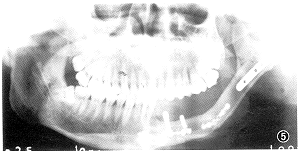

(本文图5见插页第24页)

图5 同图4患者术后半年颌骨曲面断层片像。腓骨中段截断塑形成下颌角,微夹板固定,断端已愈合